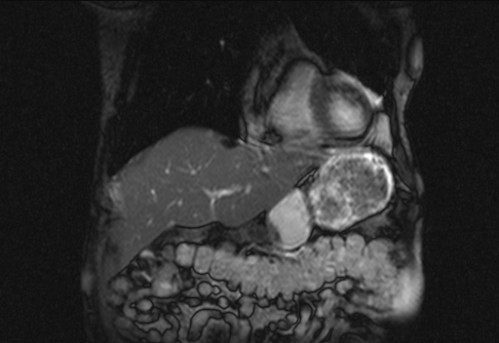

Auffälliges Abdomen bei der Vorsorgeuntersuchung einer älteren Dame

ICD: C64